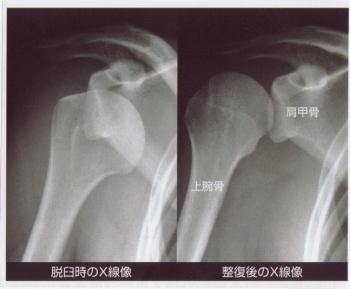

肩関節脱臼は、脱臼の中でもっとも頻度が多く、脱臼の50%以上が肩です。

前方・後方・下方・上方脱臼がありますが、ほとんど前方脱臼です。

肩関節脱臼(前方脱臼)の症状

肩関節が約30°外転し、上腕骨が外転内旋している

三角筋部の膨隆が消失し、肩峰が角上に突出する

肩峰の下が空虚となり、烏口突起の下に骨頭が触知できる

私も肩の脱臼に出会って何度も整復したことがあります。

しっかりと整復し、反復性脱臼(何度も脱臼を繰り返す)にならないようにしましょう